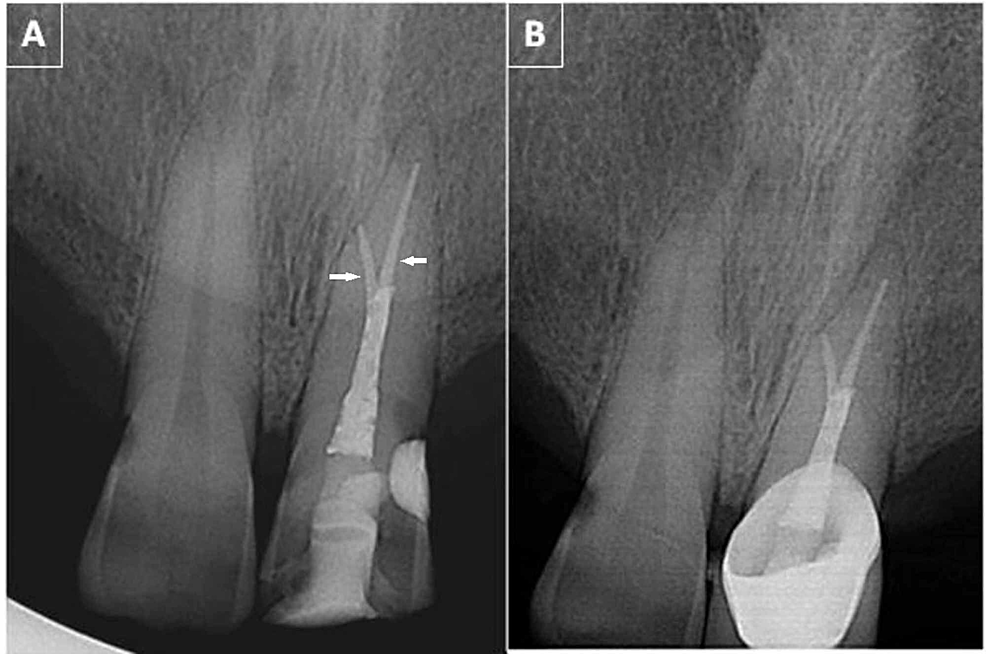

Vertical Root Fracture in Buccal Roots of Bifurcated Maxillary Bifurcated Root  A bifurcation is a juncture of two roots at the base of a tooth, which can be affected by bone loss and periodontal disease. Mandibular first premolars may also exhibit a bifurcated root, one buccal, and one lingual (fig. This chapter reviews the external and internal morphology of roots and canals, and introduces a new coding system for classifying. Find. Bifurcated Root.

Buccal root of the bifurcated maxillary premolar—a danger zone during Bifurcated Root  The mandibular first and second premolars typically present with single roots but may have bifurcated roots in rare situations. Mandibular first premolars may also exhibit a bifurcated root, one buccal, and one lingual (fig. This chapter reviews the external and internal morphology of roots and canals, and introduces a new coding system for classifying. Which of the following premolar teeth. Bifurcated Root.

Buccal root of the bifurcated maxillary premolar—a danger zone during Bifurcated Root  Mandibular first premolars may also exhibit a bifurcated root, one buccal, and one lingual (fig. Which of the following premolar teeth normally has a bifurcated root? Learn what bifurcation and trifurcation are in a tooth, how they affect the root structure and the surrounding bone, and how to treat them. Find out the causes, symptoms, diagnosis and prognosis of furcation. Bifurcated Root.

Buccal root of the bifurcated maxillary premolar—a danger zone during Bifurcated Root  Mandibular first premolars may also exhibit a bifurcated root, one buccal, and one lingual (fig. Which of the following premolar teeth normally has a bifurcated root? This chapter reviews the external and internal morphology of roots and canals, and introduces a new coding system for classifying. The mandibular first and second premolars typically present with single roots but may have. Bifurcated Root.

Vertical Root Fracture in Buccal Roots of Bifurcated Maxillary Bifurcated Root  Find out the causes, symptoms, diagnosis and prognosis of furcation involvement of a dental infection. This chapter reviews the external and internal morphology of roots and canals, and introduces a new coding system for classifying. Mandibular first premolars may also exhibit a bifurcated root, one buccal, and one lingual (fig. Learn what bifurcation and trifurcation are in a tooth, how. Bifurcated Root.